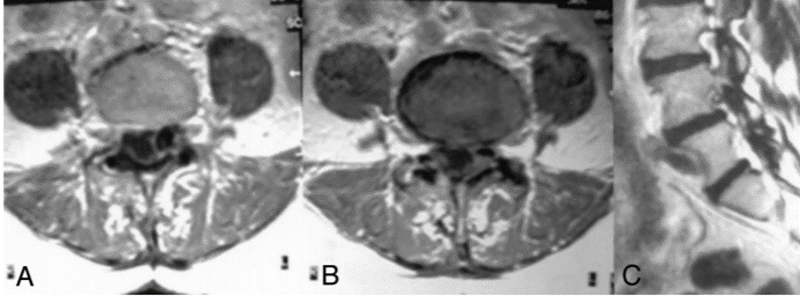

A、注射钆前轴位T1加权MRI扫描显示硬膜囊背侧有低信号钙化肿块移位;B、注射钆后,低信号区周围可见强化环;C、矢状位T2加权MRI图像。箭头显示侧隐窝内有囊性肿块